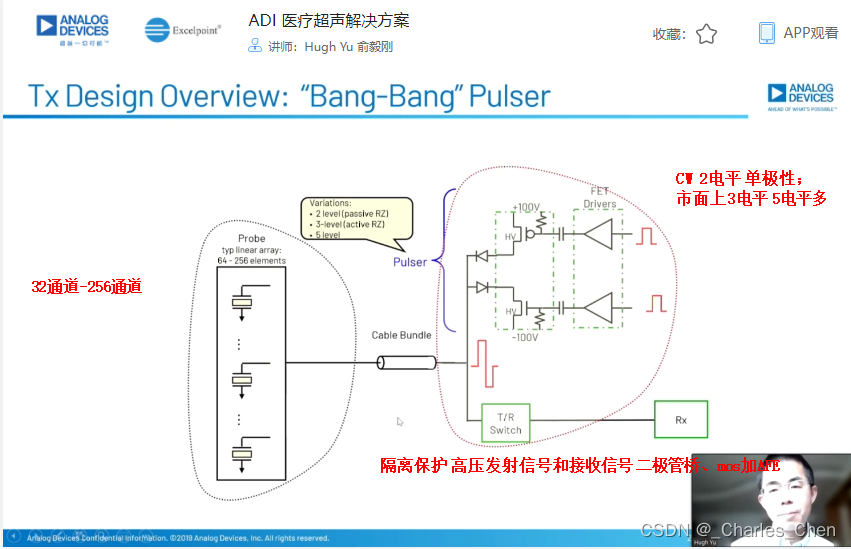

成像系统的关键器件是超声传感器。典型的超声成像系统需要使用各种传感器支持特定的诊断要求。每个传感器由一组压电传感器单元阵列构成,它们集中能量并发射到人体内部,然后接收相应的反射信号。每个单元通过纤细的同轴电缆连接到超声系统。通常,传感器由32至512个单元构成,工作频率为1MHz至15MHz。多数超声系统提供两个至四个传感器转换接口,临床医生可根据不同的检测类型方便地更换传感器。

高压复用开关

典型的相控阵超声系统配备了32至256个发射器和接收器。多数情况下,系统配备的发射器和接收器的数量少于传感器单元的数量。这些情况下,需要在传感器或系统中安装高压开关,用于信号复用,开关连接在特定的传感器单元和发送器/接收器(Tx/Rx)对之间。由此,系统能够在所提供的传感器阵列中动态改变有效的传感器孔径。

成像系统对高压开关的要求主要包括几个方面:必须能够承受电压摆幅高达200VP-P且峰值电流高达2A的发射脉冲;开关必须能够迅速切换,以快速调整有效孔径、满足图像帧率的要求;最后,这些开关还必须具有极小的电荷注入,从而避免杂散传输以及相关的虚假图像。

高压发射机

数字发射波束成形器用于产生所要求的数字发射信号,以正确的时间和相位生成聚焦发射信号。高性能超声系统可通过任意波形发生器产生复杂的发射波形,从而优化图像质量。这些情况下,发射波束成形器以大约40MHz速率生成8位至10位数字字符,并以此产生所要求的发射波形。数/模转换器(DAC)将数字波形转换成模拟信号,通过线性高压放大器进行放大,用于驱动传感器单元。由于这种发射技术占用较大体积,而且价格昂贵、需要消耗较高能量,所以,这种架构只限于昂贵的非便携设备。多数超声系统并不使用这种发射波束成形技术,而是采用多级高压脉冲发生器产生需要发射的信号。在这种替代方案中,利用高集成度、高压脉冲发生器快速切换传感器单元至适当的可编程高压电源,产生发射波形。为了产生一个简单的两极发射波形,脉冲发生器需要交替地将传感器单元切换到由数字波束成形器控制的正、负发射电压。更复杂的设计可以让传感器单元切换至多路电源和地,从而产生更复杂、性能更好的多重波形。

Tx/Rx开关

Tx/Rx开关可以保护低噪声放大器免受高压发射脉冲的影响,同时在接收间歇期间隔离低噪声放大器输入和发射机。该开关一般采用一组正确偏置的二极管阵列实现,当有高压发射脉冲出现时,它们会自动闭合或断开。Tx/Rx开关必须具备很快的恢复时间,以保证接收机在发射一个脉冲后能够立刻开启。这些快速恢复时间对于浅埋成像和提供低导通电阻确保接收灵敏度至关重要。

连续波多普勒(CWD)

多数的心脏检查和一些通用的超声成像系统中,常常使用连续波多普勒CWD以确保精确测量心脏内高速流动的血液。CWD模式下,超声传感器单元以传感器孔径为中心分割成对等的两部分。一半单元用于发射,产生CWD聚焦波束;另一半单元用于接收,产生聚焦的接收波束。发射单元的驱动波形为多普勒频率的方波,频率范围通常为1MHz至7.5MHz。发射波形的抖动必须足够小,以防止相位噪声对多普勒频移检测的影响。通过正确调整发射波形的相位,实现发射波束聚焦。类似地,通过正确调整接收波形的相位并进行叠加,实现CWD接收信号聚焦。在此模式下,发射和接收同时进行,有用的多普勒信号频率和不移动的人体组织在发射基波频率下产生的强反射信号的频率相差只有几kHz。处理如此大的信号所需要的动态范围已经超出了图像接收通道VGA、AAF和12位ADC可以承受的范围。因此,CWD必须使用其它高动态范围接收解决方案。